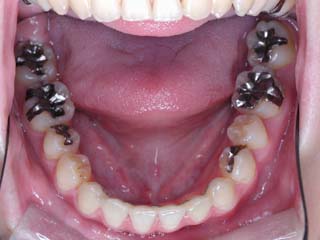

主訴:上の歯が出ている

診断名:顎関節症、上顎前突、叢生を伴う開咬

年齢:20歳

使用した主な装置名:TPB、マルチブラケット装置

抜歯/非抜歯および抜歯部位:抜歯(上顎左右第一小臼歯、下顎左右第二小臼歯)

治療期間:動的処置2年3か月、経過観察3年

費用の目安:保険適応 自己負担金として30~50万

リスク、副作用:外科手術によるリスク、マルチブラケット治療に伴う歯根吸収など偶発症が発生するリスクがある。

比較的強い叢生と、下顎の劣成長を伴う開咬が見られます。成長を終了した永久歯列ですので、骨の大きさのズレへのアプローチは大きく別れる所です。程度が小さければ、歯の傾きで補うように解決しますし、大きなズレであれば、外科的に骨のズレを改善する治療が選択されます。垂直的な問題はその他の不正咬合と比較して、解決が極めて困難な事が多いです。治療後の後戻りが頻繁に見られる不正咬合ですので、外科矯正での改善が望ましい場合も多いでしょう。

術前矯正の仕上げにスプリント治療を行った方が良い場合が多いです。現在、当院での治療では、術前に3か月のスプリント治療を必須にしております。せっかく手術までしてかみ合わせの位置を合わせようとしているのに、顎の関節の位置がずれていたらどうなるでしょう。顎の関節は往々にして顎の大きさのズレをカムフラージュするような偏位を示すので、術後にじわじわと後戻りしているような現れ方で、ズレが見えてくるのでは?このスプリント治療を徹底できたケースでは術後の安定性が極めて高いと感じています。

外科手術は、上顎のインパクションのみをLeFort1にて行いました。